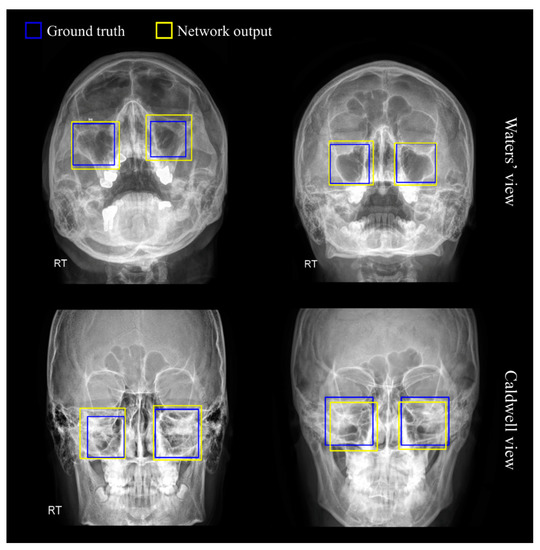

Figure 3 illustrates the sinus detection results obtained by RetinaNet, where the blue boxes refer to the gold-standard of maxillary regions, and the yellow boxes indicate the prediction results. As observed in the figures, the detection results of sinus were satisfactory in both views; the degree of discrepancies between the two boxes can be considered negligible. Multiple bounding box coordinates were recommended by the RPN as possible candidates for the left or right sinuses, and the sinus region with the highest probability was finally selected and cropped.

Figure 3. Representative examples of maxillary sinus detection results via RetinaNet. The blue bounding boxes indicate the ground truth and the yellow boxes indicate the prediction results of the neural network.